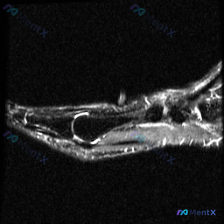

髋关节MRI读片分享:大转子周围软组织高信号的分析思路

拿到这张髋关节冠状位T2序列MRI,先整理一下影像基本信息:

扫描范围覆盖右侧髋关节,包含股骨头、股骨颈、股骨近端、髋臼及部分盆腔结构,解剖结构清晰,股骨头形态正常,髋臼包绕股骨头形态正常。

- 骨骼与关节内结构:股骨头骨髓信号没有异常高低改变,没有缺血性坏死典型的双线征,也没有大片骨髓水肿;股骨头关节面皮质光滑完整,关节间隙宽度正常,关节囊内没有明显异常积液高信号,基本排除了典型关节腔积液。

- 盂唇情况:髋臼外上缘盂唇有局灶性信号增强。

- 软组织异常(核心发现):在大转子上方及侧方的外展肌群(臀中肌/臀小肌)附着点区域,可见明显条片状T2高信号,提示这里存在软组织水肿或者炎症改变;大转子周围滑囊没有明显巨大积液,周围肌肉形态正常,没有明显萎缩。